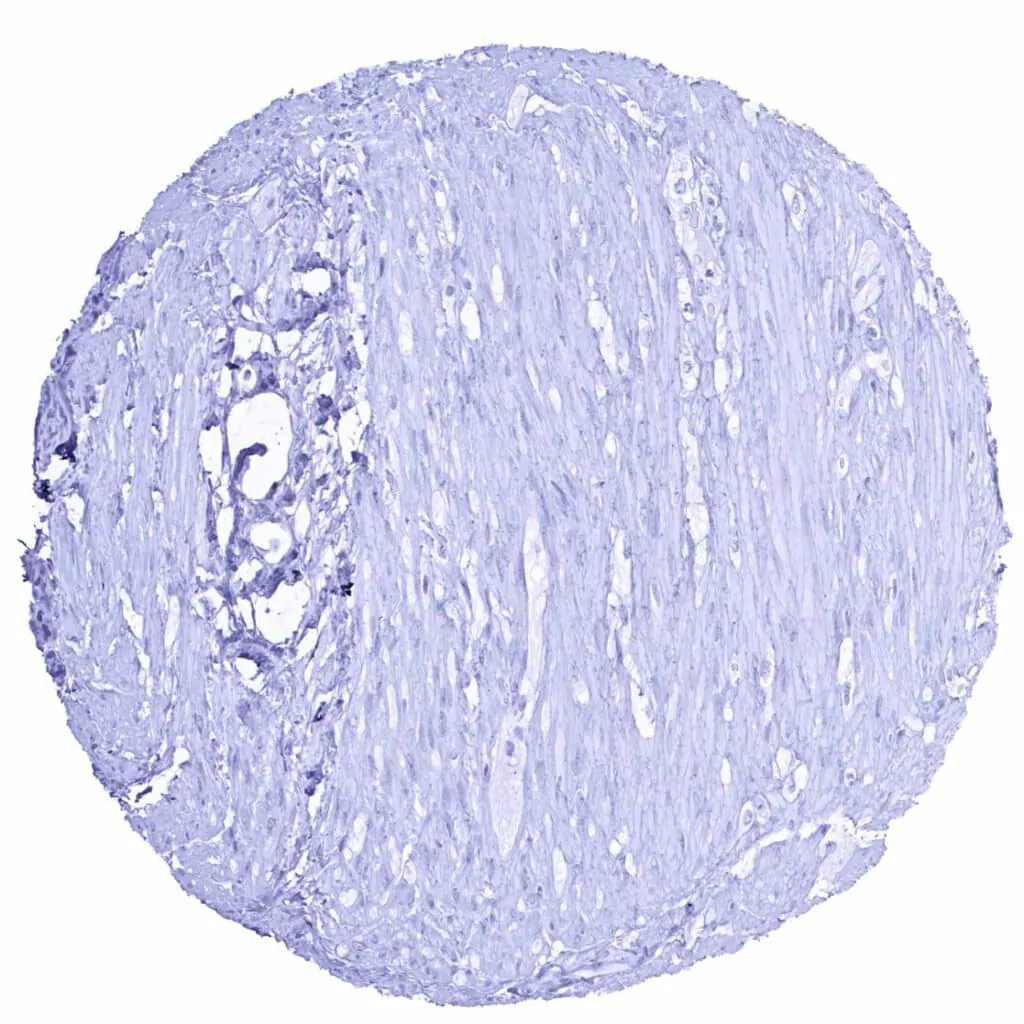

Uterus, myometrium